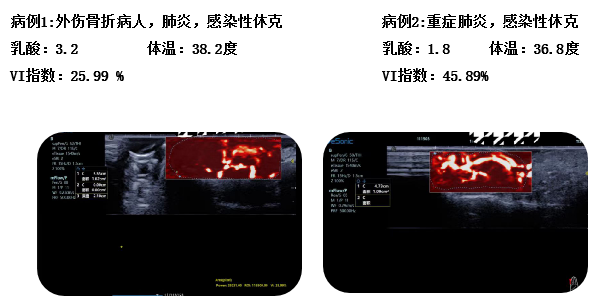

eHertz新技术助力急重症新突破---mFlow开创感染性休克,微循环灌注评估新思路

彩色多普勒成像、3D壁滤波原理;血流敏感度明显提升,分辨率达100微米;支持灰阶和微血流量同步测量、可测极低速血流的速度;多种模式,多数据定量

急重症应用:重症肾移植病人肾脏的评估;急性肾损伤评估;微循环灌注;感染性休克。